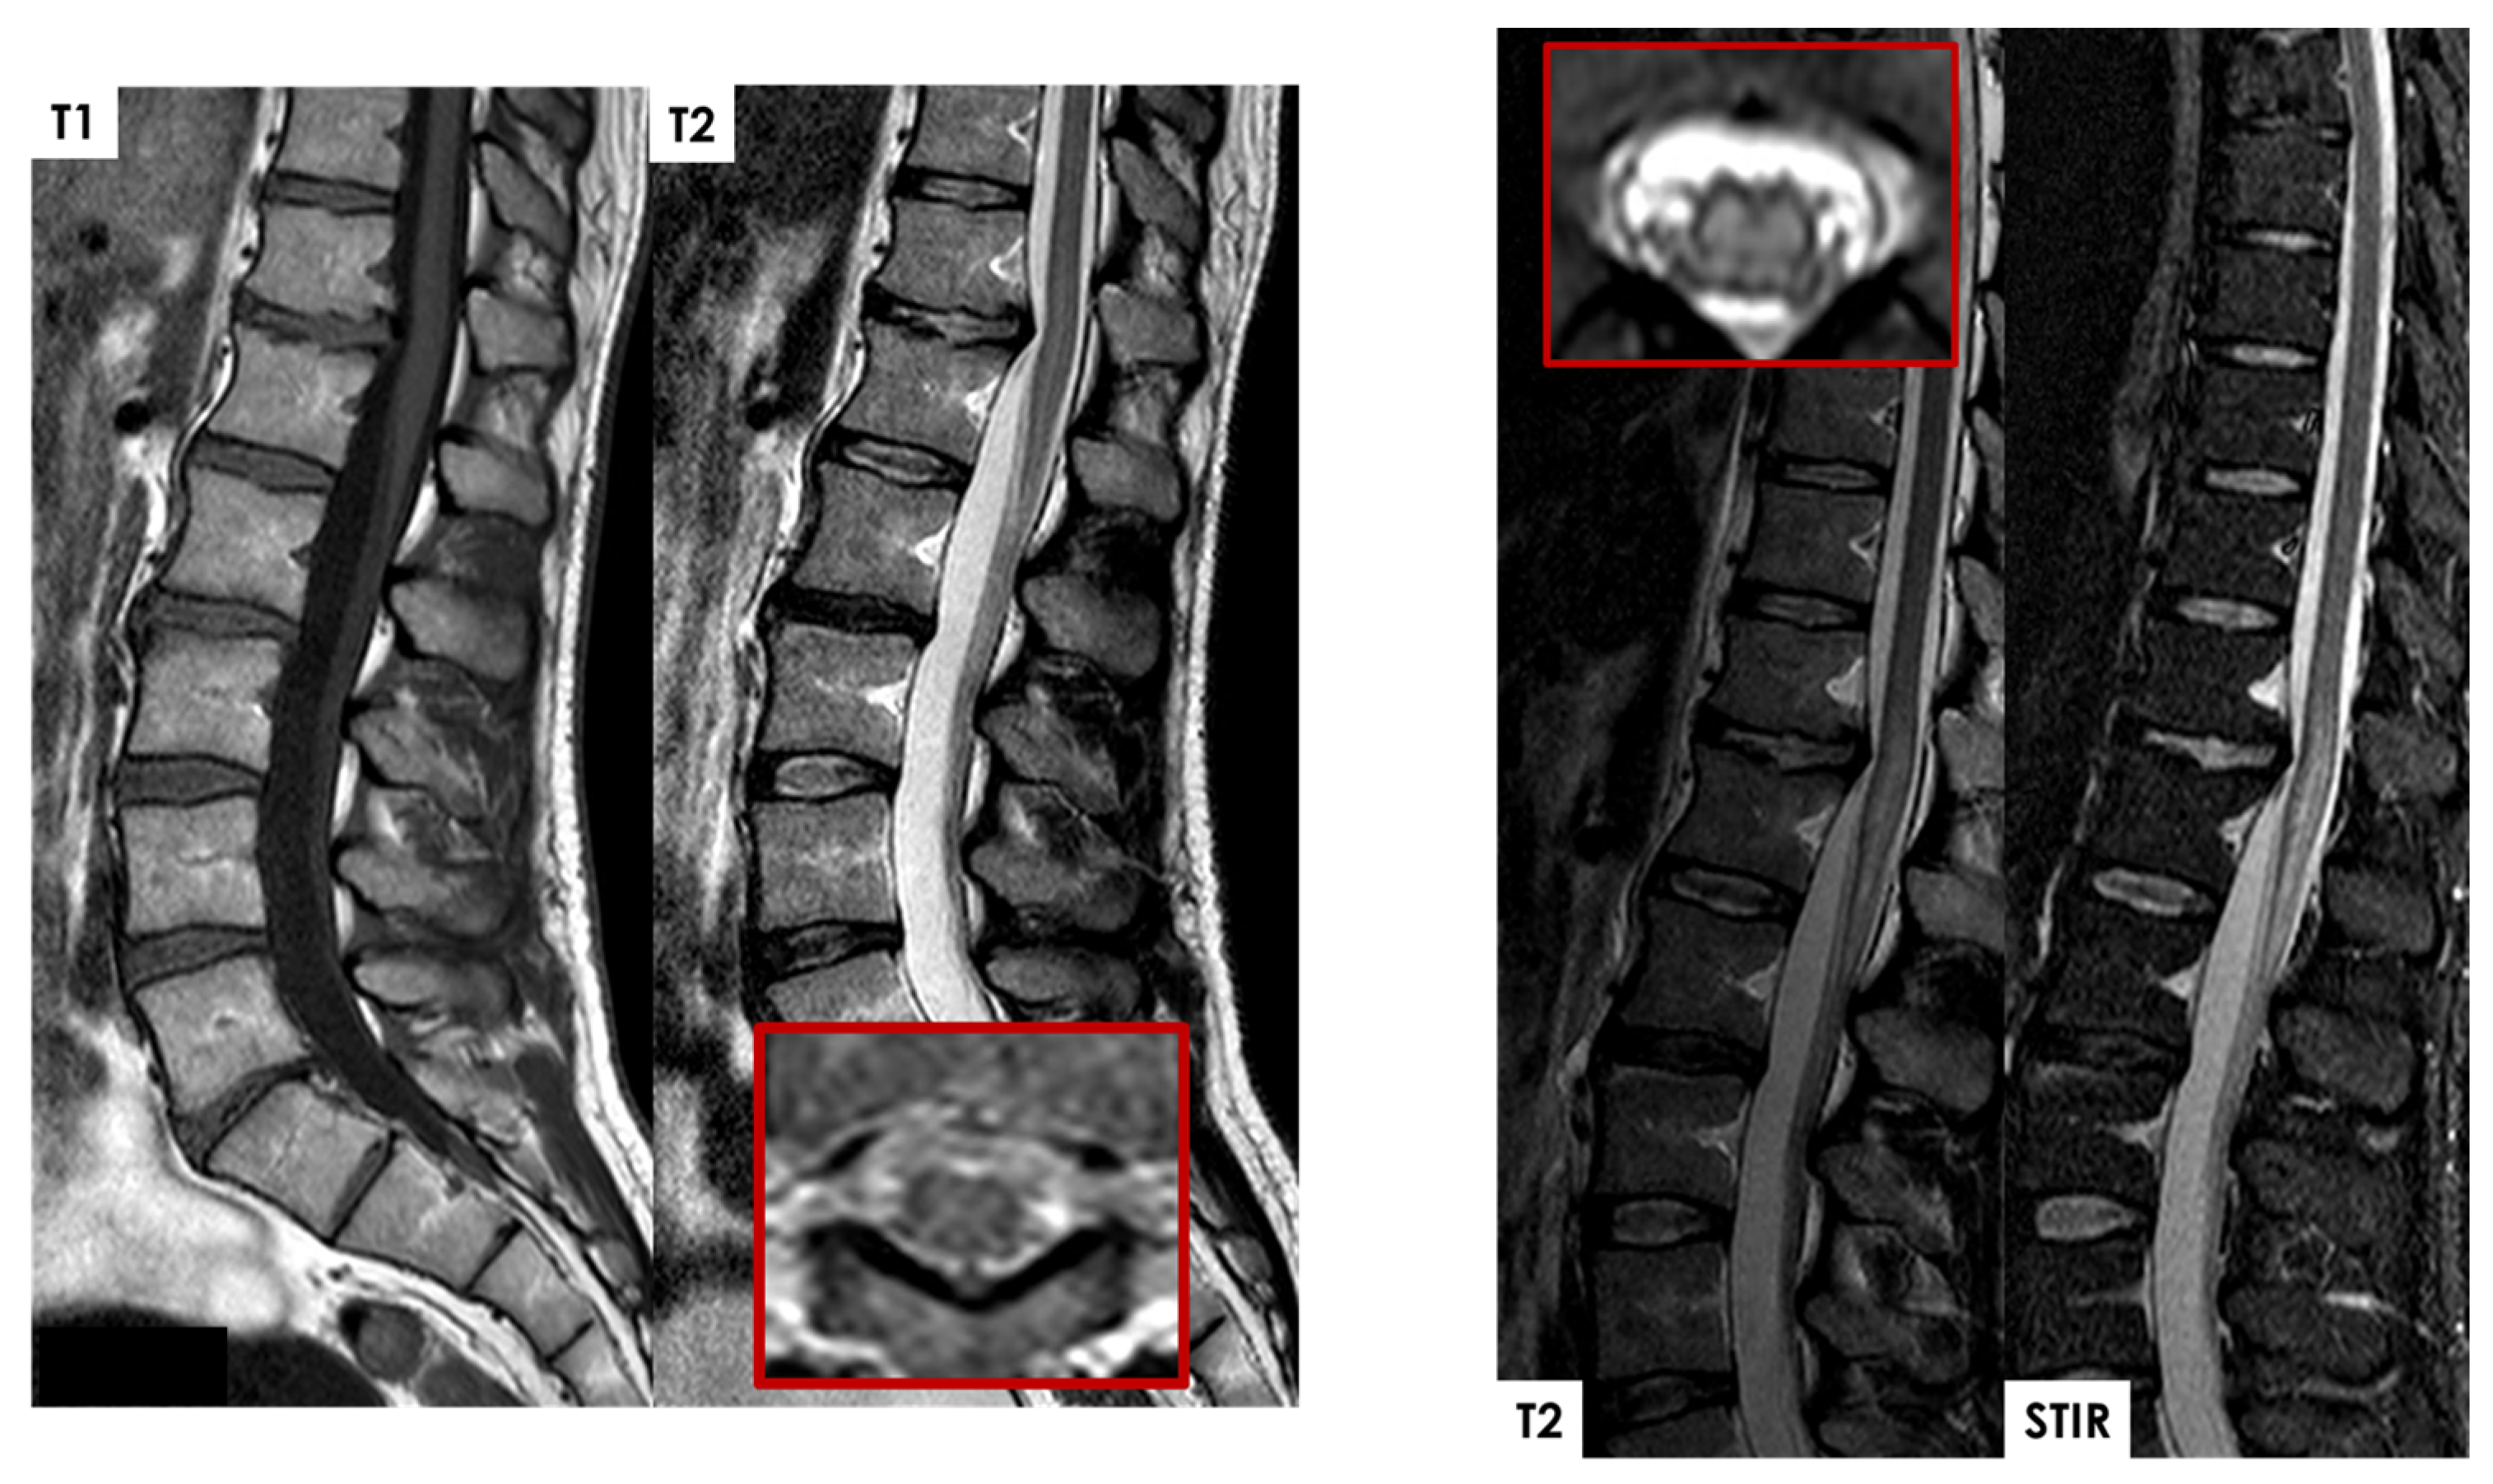

- In the hyperacute and acute phases, parenchymal T2-hyperintensity appears non-expansile, thin, and pencil-like on sagittal images;

- In the later acute and early subacute phases, spinal cord enlargement may occur;

- Vertebral body infarcts may also be observed.